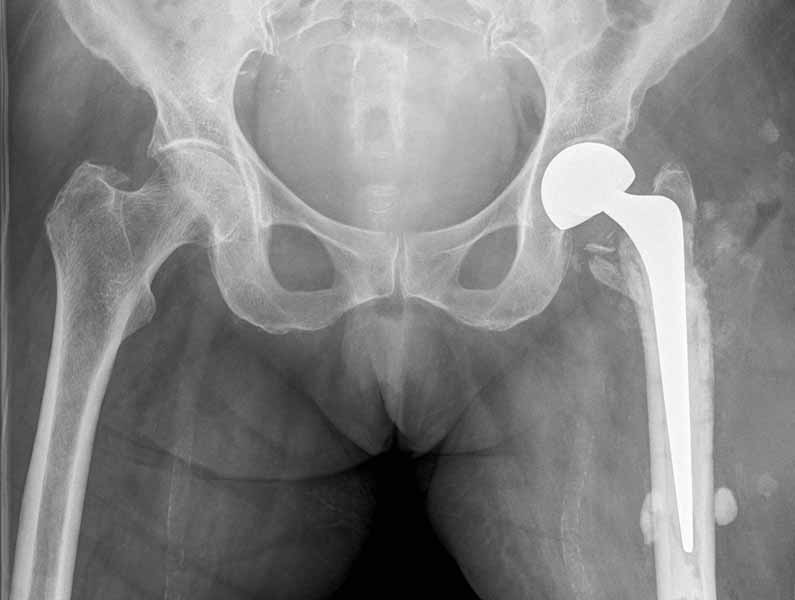

Имя     : 51340089.jpg